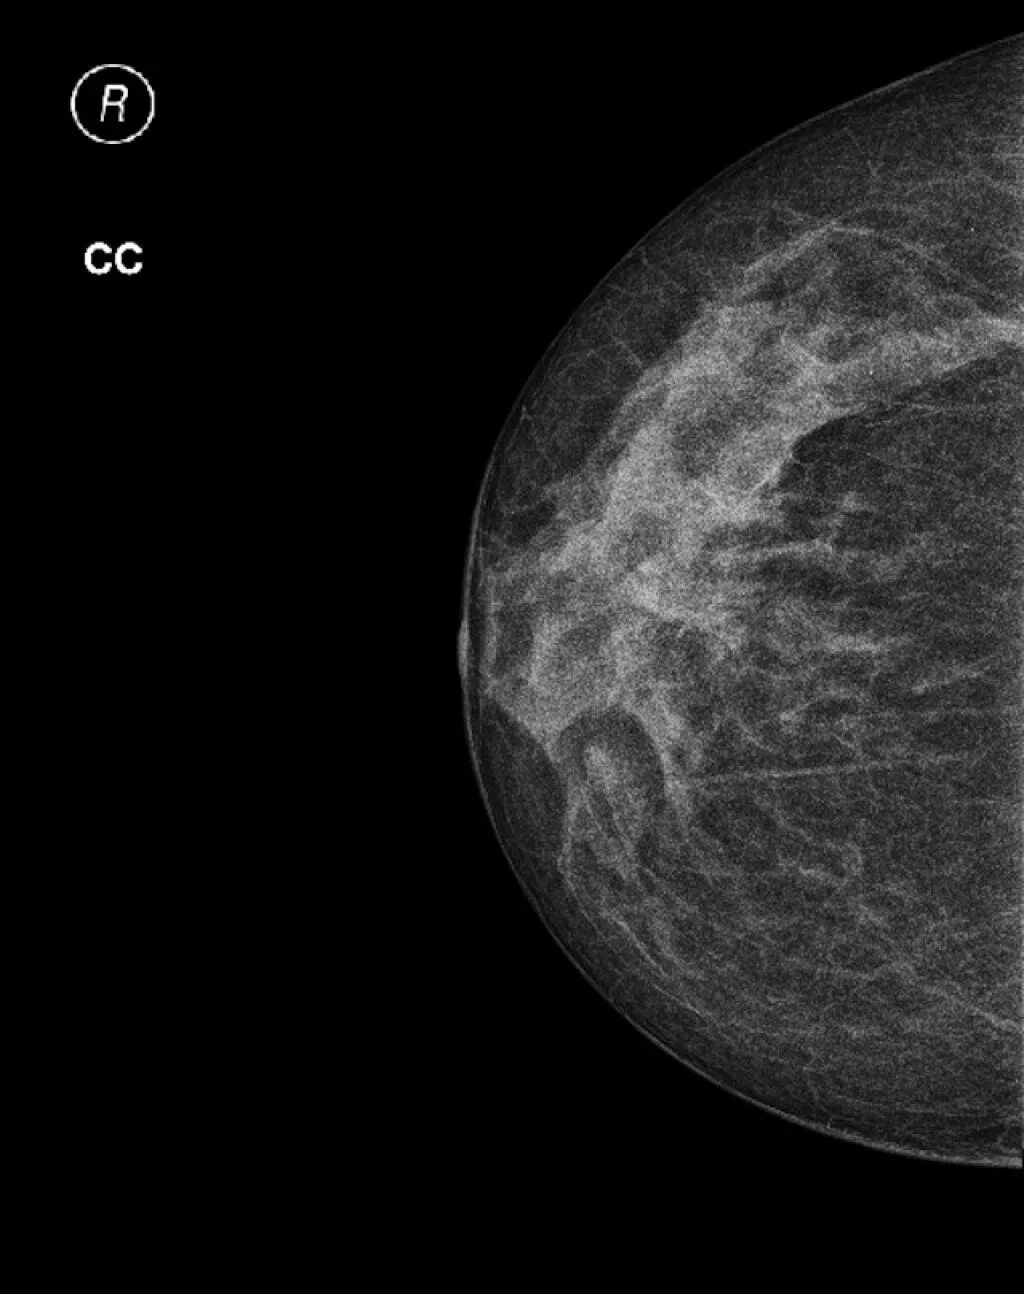

Склерозирующий аденоз молочных желез